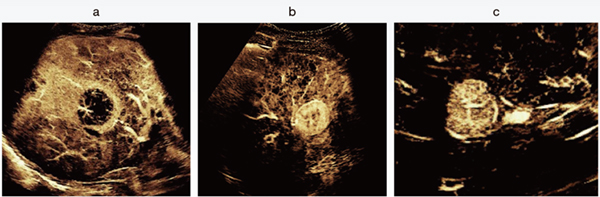

図2 Super Resolution MVIによる肝腫瘍の血管構築パターン

a:転移性肝がん b:肝細胞がん c:限局性結節性過形成